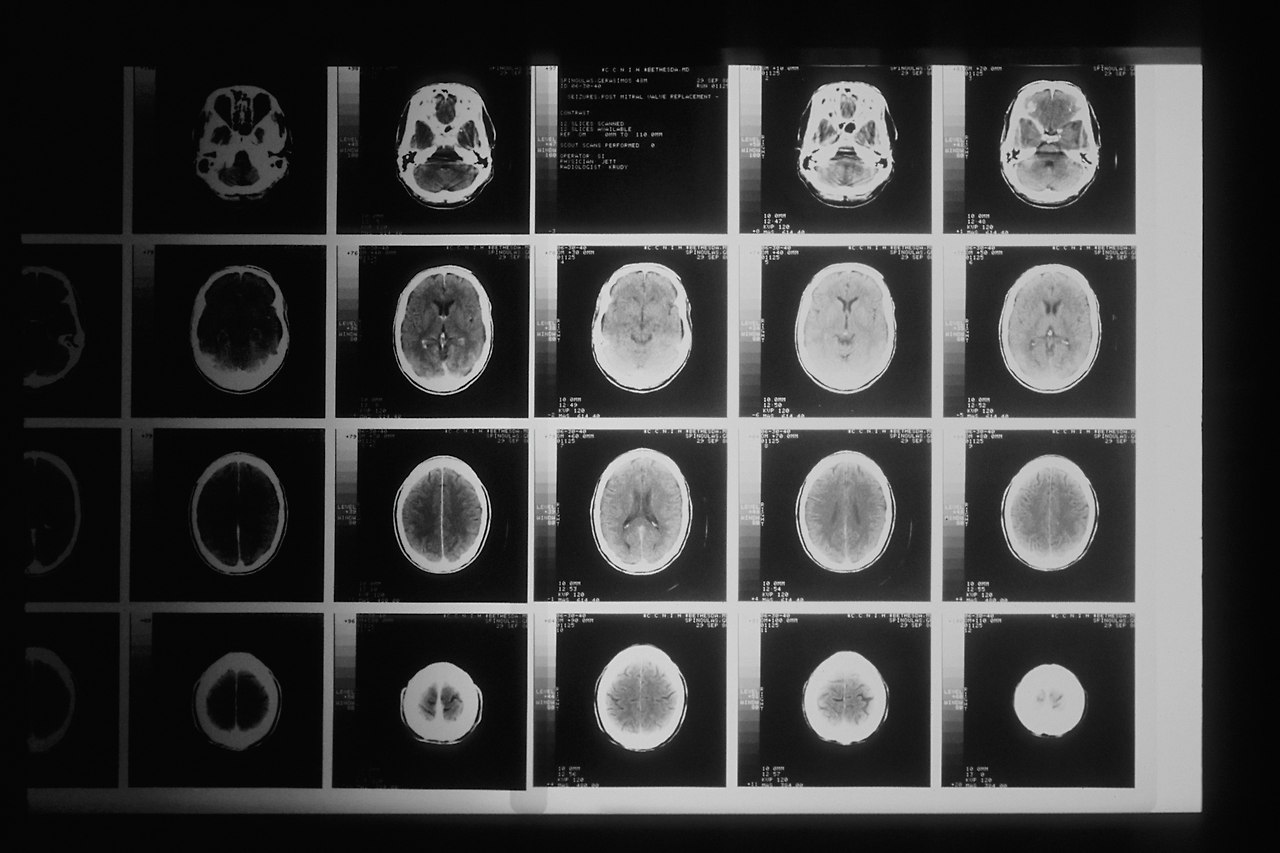

가장 안 좋은 상황이 바로 관상동맥에 쌓이는 것이다. 관상동맥에 칼슘이 얼마나 쌓였는지 알아보는 점수 체계로 CAC(Coronary Artery Calcium) 점수라는 게 있을 정도다. <저탄고지 바이블>을 쓴 아이버 커민스와 제프리 거버는 심혈관계 건강 관리를 위해 이 점수가 제일 중요하다고 주장한다. 그래서 관상동맥에 CT를 주기적으로 쏴주라는 (나로서는 본말이 전도된 것으로 밖에는 안 보이는) 조언을 할 정도다.

national-cancer-institute-BDKid0yJcAk-unsplash.jpg 사진: Unsplash의National Cancer Institute

관상동맥 칼슘 침착은 칼슘과 비타민 D의 체내 농도와 상관없이 일어나는 현상이다. 즉, 이 현상은 몸이 고장 났다는 증거다. 실제로 <저탄고지 바이블>은 CAC 점수를 전반적인 몸의 건강 척도로 활용해야 한다고 말하고 있다. 단지 관상동맥 관리나 심혈관계 질환 방지를 위해서 CT 촬영을 매년 하라는 얘기가 아니다. 이 책의 저자들은 관상동맥에 칼슘이 쌓이는 현상이 인슐린 저항성의 결과라고 주장한다. 책에는 저탄수화물 고지방 식이요법을 통해 CAC 점수를 낮춘 환자들의 사례가 다수 소개되어 있다.